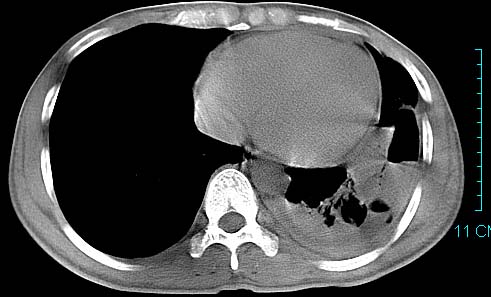

以下是引用ctkz987在2006-3-28 13:04:00的发言:[br]左侧胸腔积液穿刺后多发气液平(多房性),结合临床有高热不除外合并感染。

以下是引用qian在2006-3-28 14:32:00的发言:[br]左肺下叶大片状阴影,密度不均,见有条片影和空洞及气液平,少量胸腔积液伴有胸膜增厚,从图像看积液密度比水的密度高,结合病史,考虑左下肺化脓性炎症伴有脓胸。

以下是引用wawaquan在2006-3-28 22:25:00的发言:[br]左上肺舌段多发斑片影。结合“男24y咳嗽咳痰气促伴高热(38.5--39.5)20多天”及穿刺史,[br]考虑1 左下肺化脓性炎症;2脓胸。

以下是引用乡医在2006-3-28 18:37:00的发言:[br]左侧多发液气平面结合患者男24y咳嗽咳痰气促伴高热(38.5--39.5)20多天,查胸水:ldh239.3,总蛋白59.19,tb-ab阴性,利凡它试验+,红c2.7*109,白c1.08*109,分类淋巴92%分叶8%,考虑1脓胸2肺隔离征感染